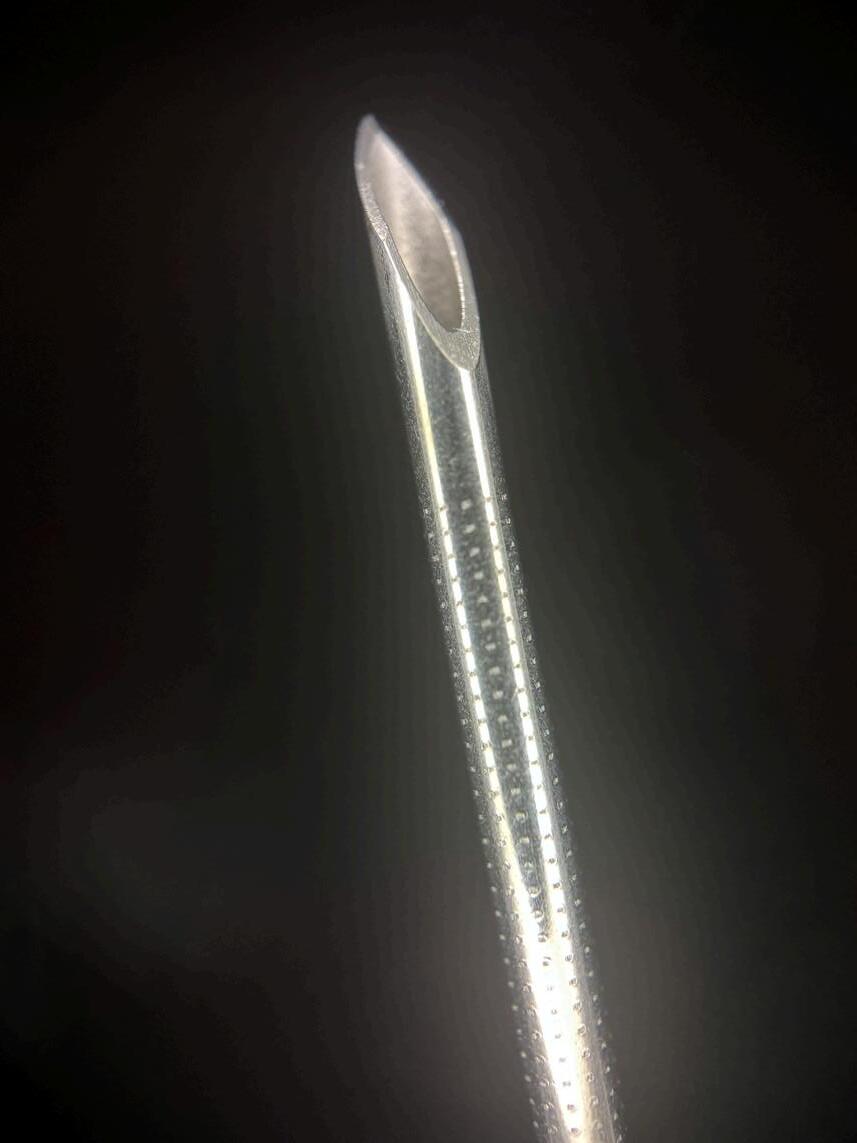

Igła to jedno z najczęściej używanych narzędzi w medycynie. Pielęgniarce w obrazie wykreowanym przez media często towarzyszy atrybut w postaci strzykawki z igłą. W zasadzie nie bez przyczyny- zarówno procedury rutynowe, jak i te ratujące życie, często wymagają iniekcji. Dla większości pacjentów te czynności są krótkotrwałym dyskomfortem, który szybko mija. Jednak dla części osób nawet sama myśl o igle staje się źródłem intensywnego stresu, a nawet paraliżującego lęku. Needlefobia- czyli fobia związana z igłami i procedurami iniekcyjnymi – sprawia, że pacjenci unikają kontaktu z ochroną zdrowia, odkładają szczepienia czy rezygnują z koniecznych badań. Ten mechanizm działa jak efekt kuli śnieżnej: unikanie drobnych procedur profilaktycznych może prowadzić do późnego rozpoznania poważnych chorób, braku wdrożenia leczenia we właściwym czasie. W konsekwencji needlephobia nie jest już wyłącznie problemem indywidualnym- jej skutki odczuwalne są także w skali zdrowia publicznego Odkładane diagnozy i powikłania chorób generują wyższe koszty leczenia, obciążają system opieki zdrowotnej i mają realny wpływ na jakość życia pacjentów. W tym kontekście szczególnego znaczenia nabiera rola pielęgniarki. To właśnie ona jest najczęściej osobą wykonującą procedury z użyciem igły, a jej postawa i sposób komunikacji mogą decydować o tym, czy pacjent poczuje się bezpiecznie. Nawet tak „banalne” czynności jak szczepienie czy pobranie krwi wymagają uważności, empatii i indywidualnego podejścia Zorientowanie na pacjenta - spokojne tłumaczenie kolejnych etapów, wsparcie emocjonalne czy stworzenie atmosfery zaufania, może nie tylko zmniejszyć

Z drugiej strony należy pamiętać, że do ich obsługi konieczne jest stosowanie specjalnych igieł Hubera, a sam zabieg implantacji wymaga interwencji chirurgicznej i wiąże się z wyższym kosztem początkowym. Pomimo tych ograniczeń port naczyniowy pozostaje rozwiązaniem wygodnym i bezpiecznym dla pacjentów wymagających przewlekłego dostępu do dużych naczyń żylnych.